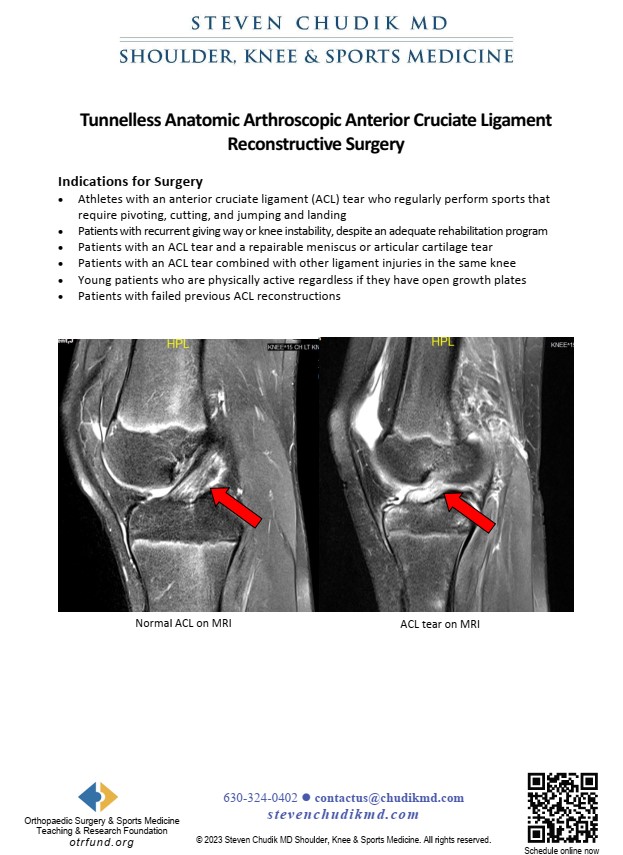

Dr. Chudik has filed patents and developed less invasive tunnelless techniques and instruments to reconstruct the ACL and PCL without drilling large tunnels in the bones of the femur and tibia and better reproducing the normal anatomy and function of the ligaments. Under development. This special procedure is currently under development.